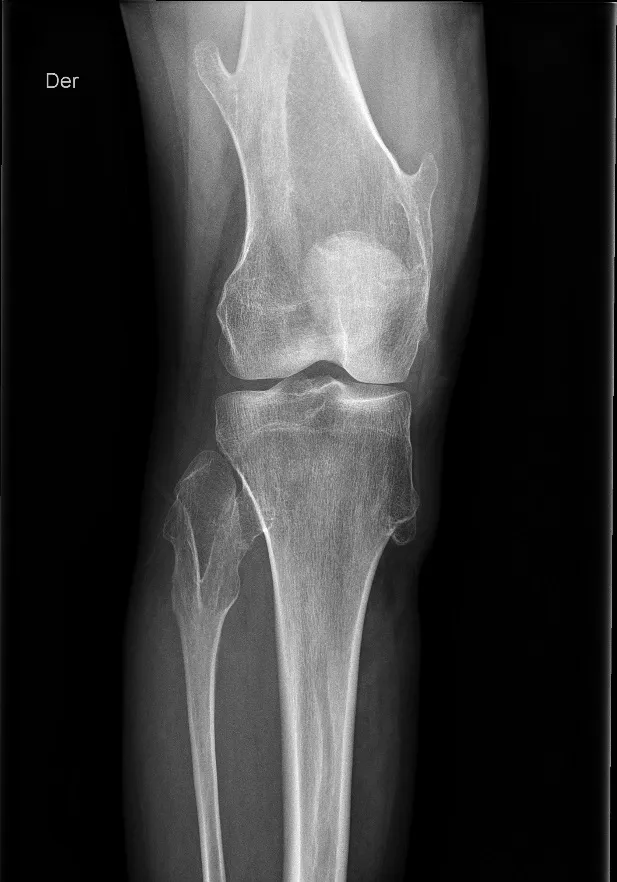

Rx de rodilla derecha en un paciente joven. Se observan múltiples exostosis en el fémur distal y la tibia proximal, que provocan, además, un ensanchamiento de la metáfisis del peroné proximal.

La exostosis hereditaria múltiple (EHM) es un trastorno autosómico dominante que se manifiesta por la presencia de múltiples osteocondromas, tumores benignos que sobresalen de la superficie ósea. Las exostosis pueden ser sésiles o pediculadas y se localizan en las metáfisis o cerca de ellas. Si bien los osteocondromas son lesiones benignas, en ocasiones provocan deformidades esqueléticas que, a su vez, pueden causar síntomas clínicos. Estas masas, inicialmente indoloras, pueden volverse dolorosas al comprimir tendones, músculos o nervios.

La complicación más grave es la posibilidad de que una exostosis sufra una transformación maligna en condrosarcoma. En pacientes con madurez esquelética, se debe medir el casquete cartilaginoso en RM. Si este tiene un grosor superior a 1 cm, existe un mayor riesgo de malignidad.